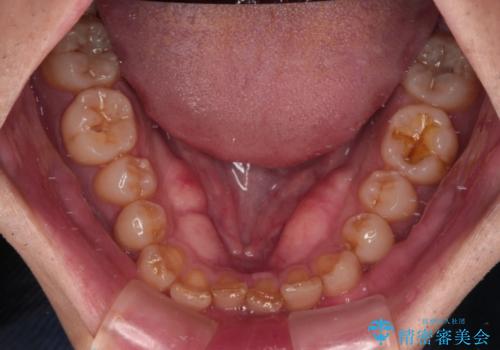

- 前歯のデコボコと深い咬み合わせを気にして来院された患者様です。

骨格的に上顎骨がやや前方にあり、それが原因で下顎前歯が隠れるほどのディープバイトになっている状態でした。